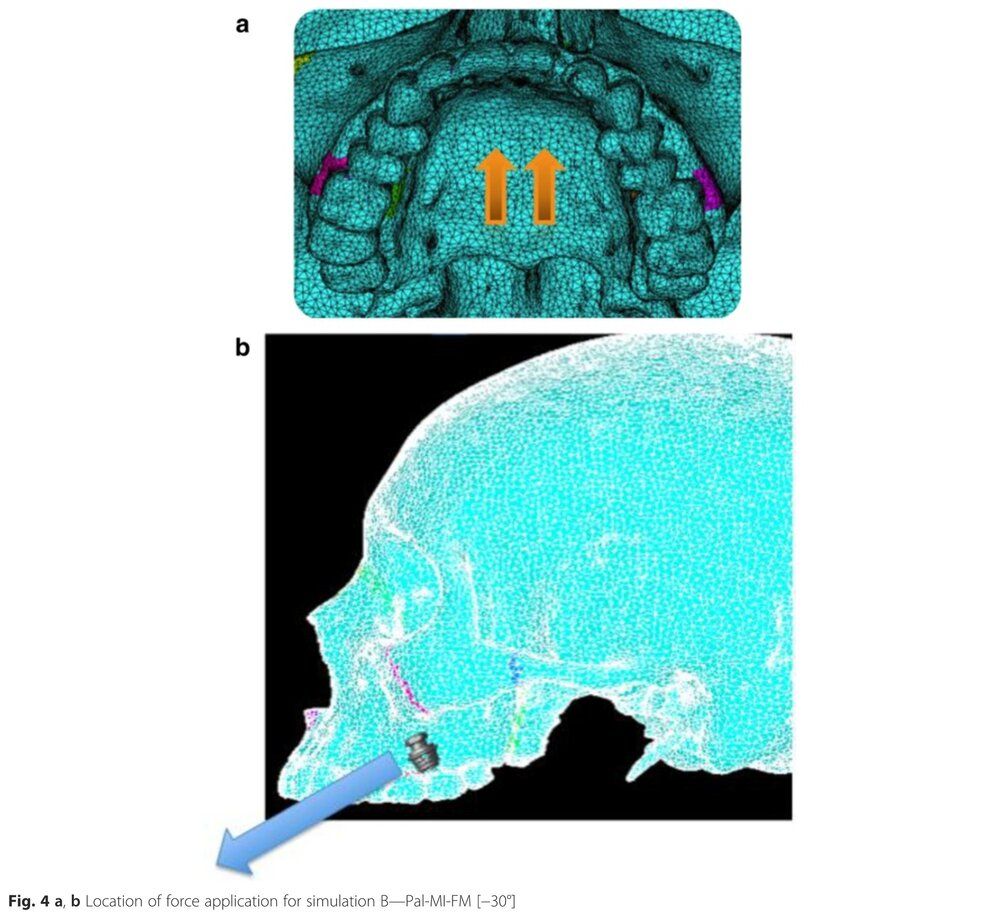

But ANOTHER thing to put into consideration is location of the micro-implant placement during facepulling - a.k.a pulling upwards exclusively. The girl from the previous study pulled downwards, 30 degrees up instead of down should give her at least 3x faster and better results. Pulling upwards was the ONLY direction that resulted in high levels of compression on all of the circummaxillary sutures, which is what generates the bone for forward growth

Look at this paper: https://scinapse.io/papers/1603230182

From this paper this is the typical maxilla displacement resulting from a microimplant assisted palate expander like MSE, Hyrax using a facepuller at a -30 degrees angle:

Look at how insignifiant is the forward displacement and how it displace your maxilla downward.

Now look at the displacement if the micro-implant was placed in a better location with a pulling angle of -15 degrees (Simulation C, picture on the right on the second picture) :

look at how signifiant is the forward displacement, look at how the maxilla rotate ccw.

But ANOTHER thing to put into consideration is location of the micro-implant placement during facepulling - a.k.a pulling upwards exclusively. The girl from the previous study pulled downwards, 30 degrees up instead of down should give her at least 3x faster and better results. Pulling upwards was the ONLY direction that resulted in high levels of compression on all of the circummaxillary sutures, which is what generates the bone for forward growth

Look at this paper: https://scinapse.io/papers/1603230182

From this paper this is the typical maxilla displacement resulting from a microimplant assisted palate expander like MSE, Hyrax using a facepuller at a -30 degrees angle:

Look at how insignifiant is the forward displacement and how it displace your maxilla downward.

Now look at the displacement if the micro-implant was placed in a better location with a pulling angle of -15 degrees (Simulation C, picture on the right on the second picture) :

look at how signifiant is the forward displacement, look at how the maxilla rotate ccw.